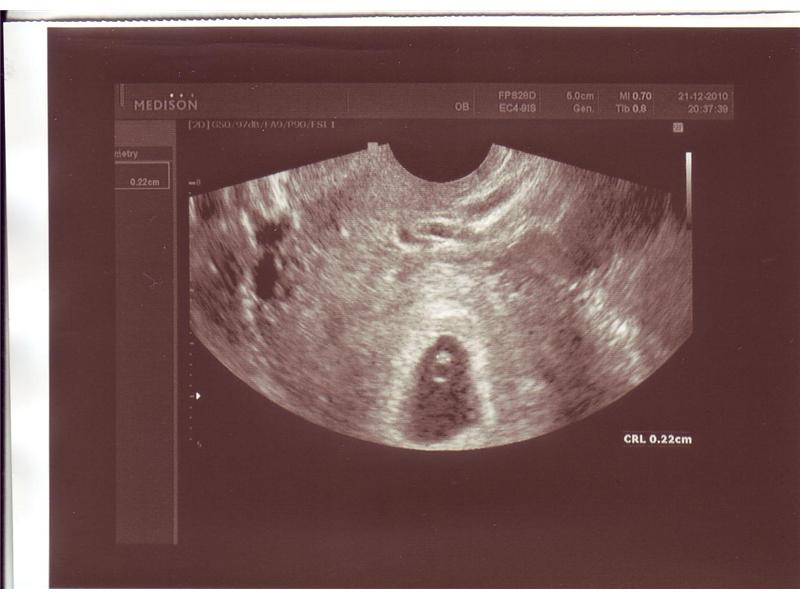

utz